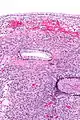

Micrograph showing a mucinous cystadenoma of the ovary. H&E stain. | |

Mucinous cystadenoma is a benign cystic tumor lined by a mucinous epithelium.